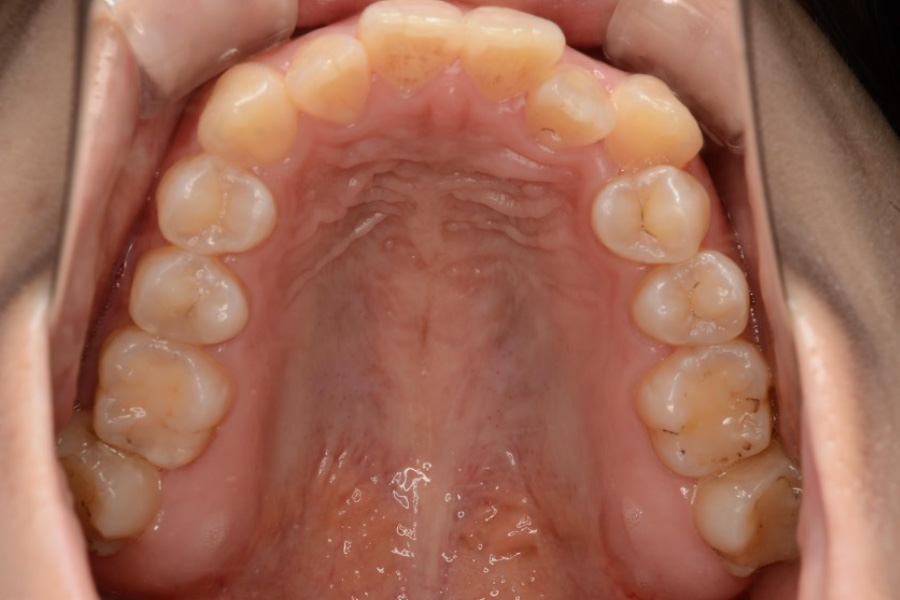

治療後

主訴 歯のガタつき

期間 2年半

治療内容 インビザライン矯正

非抜歯

治療に伴うリスク 矯正終了後は、リテーナーを指示通りに使用し、歯の後戻りを防ぐ必要があります。